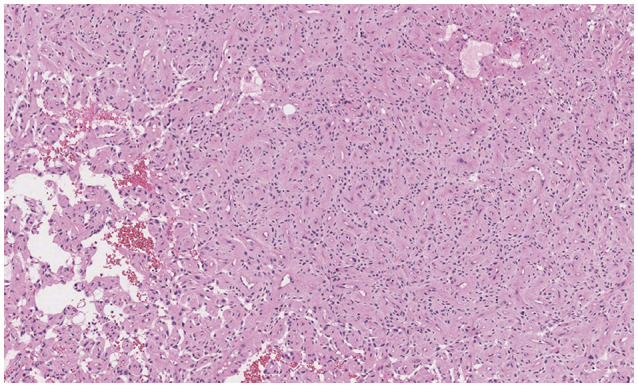

- Delayed cerebral necrosis is a well-known complication of radiation therapy (RT). Because of its irreversible nature, it should be avoided if possible, but avoidance occurs at the expense of potentially compromised tumor control, despite the use of the modern advanced technique of conformal RT that minimizes radiation to normal brain tissue. Risk factors for radiation-induced cerebral necrosis include a higher dose per fraction, larger treatment volume, higher cumulative dose, and shorter time interval (for re-irradiation). The same principle can be applied to proton beam therapy (PBT) to avoid delayed cerebral necrosis. However, conversion of PBT radiation energy into conventional RT is still short of clinical support, compared to conventional RT. Herein, we describe two patients with excessively delayed cerebral necrosis after PBT, in whom follow-up MRI showed no RT-induced changes prior to 3 years after treatment. One patient developed radiation necrosis at 4 years after PBT to the resection cavity of an astroblastoma, and the other developed brainstem necrosis that became symptomatic 6 months after its first appearance on the 3-year follow-up brain MRI. We also discuss possible differences between radiation changes after PBT versus conventional RT.